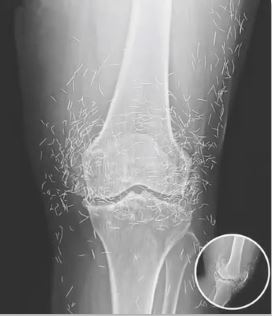

Surprising Discovery in Woman’s Knee During a Routine X-Ray Exam

When a 65-year-old woman in South Korea visited the hospital for routine knee pain, she expected a common diagnosis — arthritis. Instead, her X-ray revealed something unexpected: dozens of tiny gold needles embedded around her knee joints. The finding surprised doctors and sparked discussion about a rare alternative treatment that had gone far beyond typical medical practice.

stiffness and pain as cartilage wears down. After traditional treatments failed to ease her discomfort, she sought relief through acupuncture — a therapy widely used across Asia. However, her practitioner took an unusual approach, leaving fine gold needles permanently under her skin in hopes of providing lasting results.